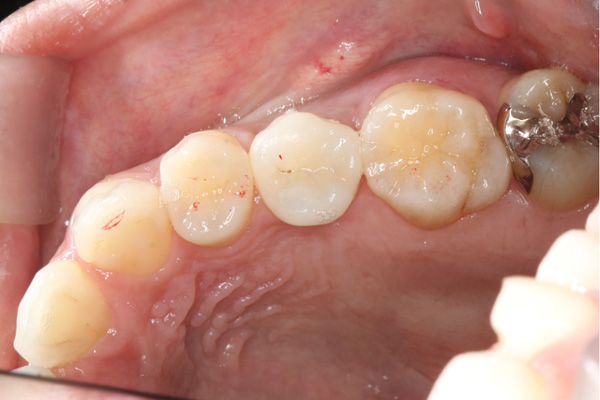

BEFORE

| 年代・性別 | 50代 男性 |

|---|---|

| 主訴 | 右下の歯がないのでインプラントをして欲しい |

| 治療期間 | 約6ヶ月 |

| 費用 | 600,000円 |

| 治療内容 | インプラント、骨造成、結合組織移植、セラミック修復 |

| 治療に伴うリスク | インプラント周囲炎 セラミックの破折、脱離 |

*キャンセルポリシーをご一読のうえご予約ください